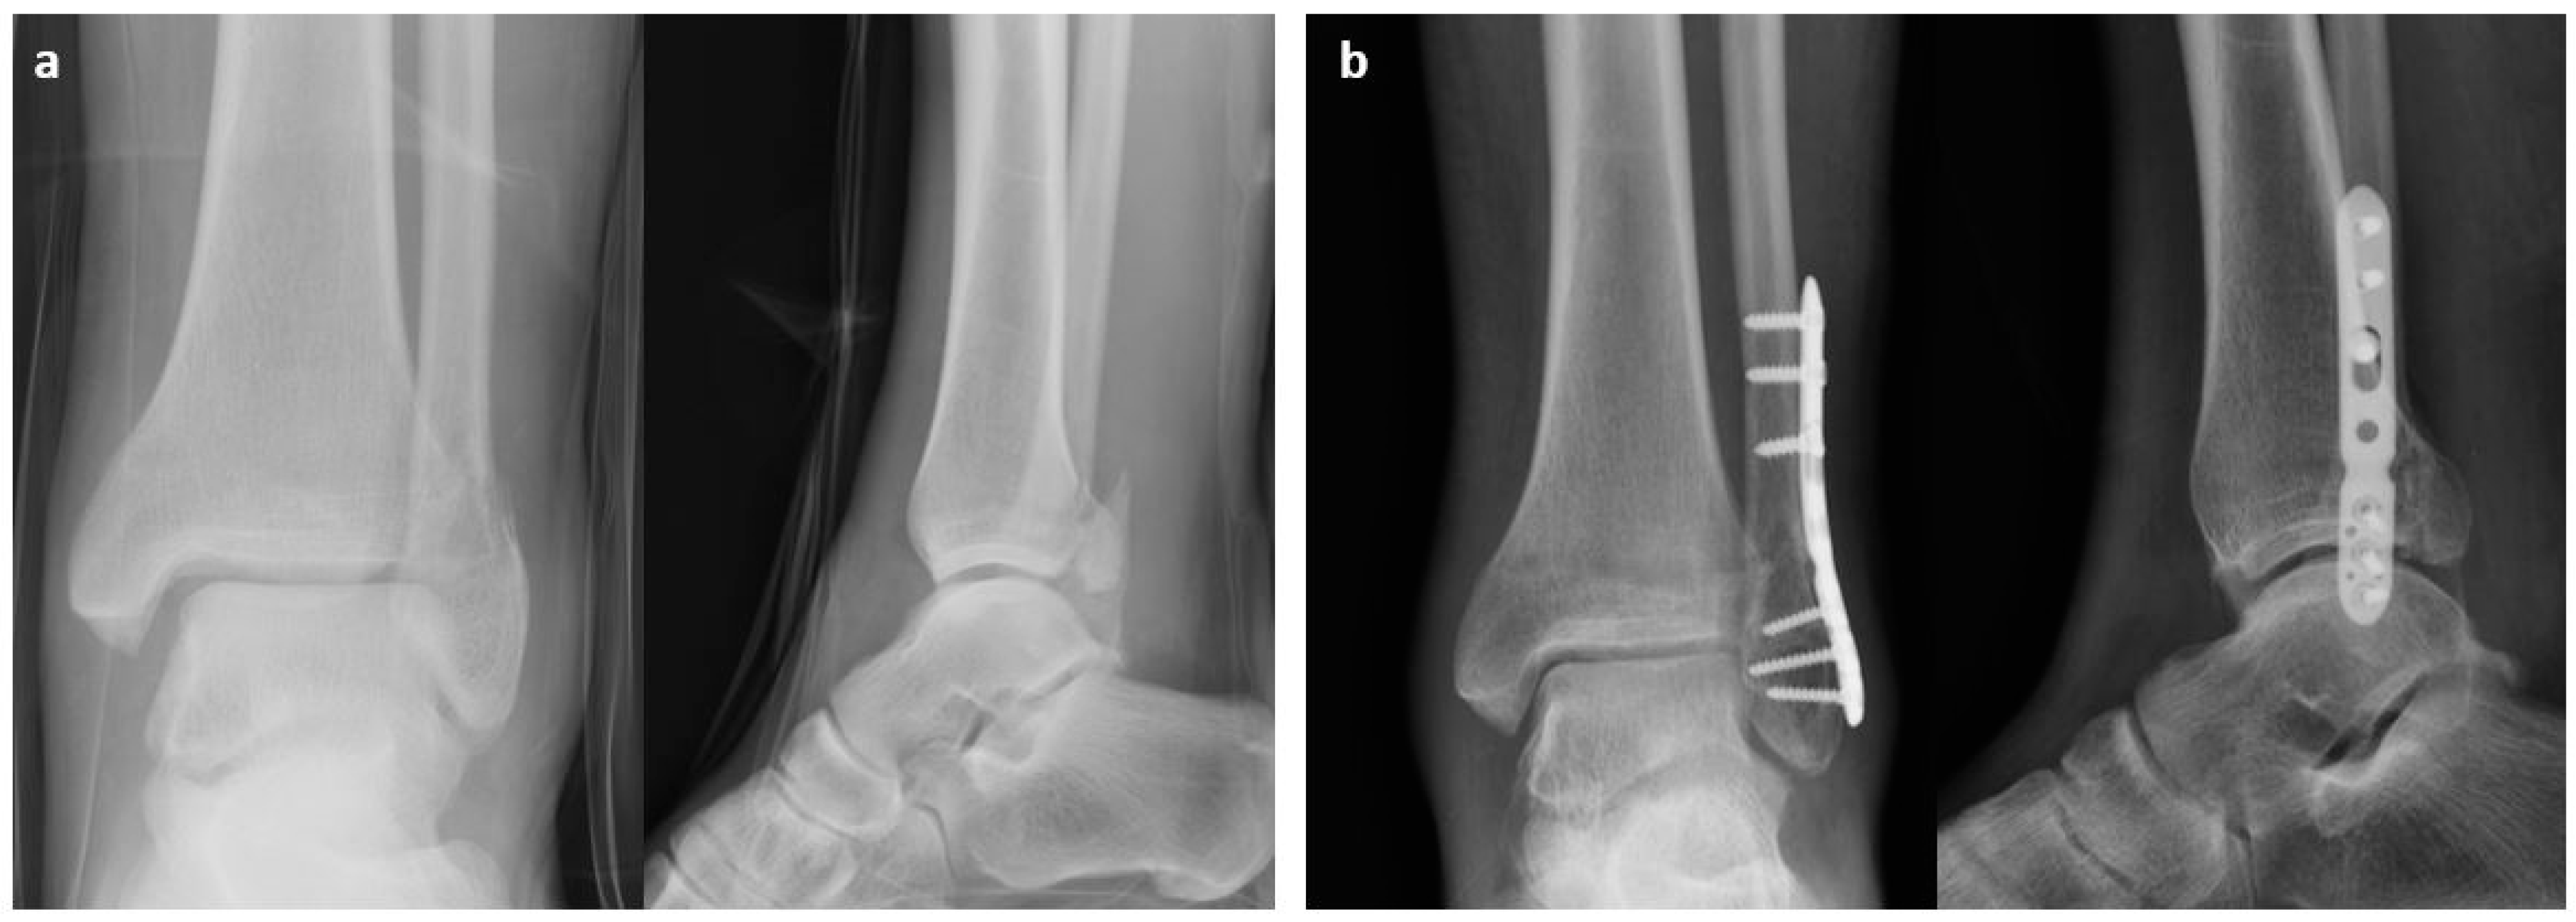

2.1. Surgical Procedure